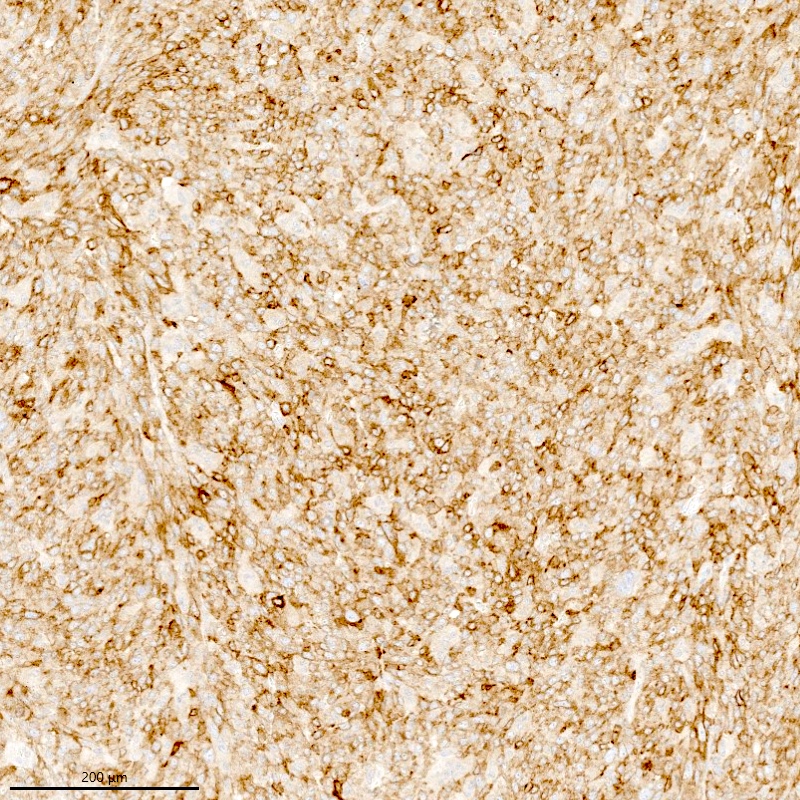

Microscopic (histologic) description

- Irregular cellular islands, forming permeative tongue-like pattern of myometrial invasion with frequent vascular invasion

- Monotonous oval to spindle cells with minimal cytologic atypia, vesicular chromatin and scant cytoplasm

- Tumor cells may whorl around delicate arteriolar type vessels, reminiscent of proliferative phase endometrial stroma

- May have admixed collagen bands / plaques and foamy histiocytes

- May have smooth muscle differentiation, particularly in a starburst morphology, with collagen bands radiating towards the periphery of the nodule

Microscopic (histologic) images

Contributed by Elizabeth Kertowidjojo, M.D., Ph.D., M.P.H. and Ayse Ayhan, M.D., Ph.D.

Positive stains

- CD10: sensitivity 91%, specificity 45% (Int J Gynecol Pathol 2018;37:372)

- IFITM1: sensitivity 83%, specificity 70% (Int J Gynecol Pathol 2018;37:372)